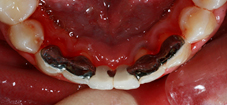

Arcade maxillaire avant traitement orthodontique, séquelles de maladie parodontale

Après traitement orthodontique et réalisation d’une attelle coulée collée (courtoisie Dr Patrick Fournier)